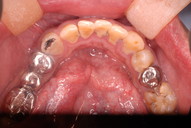

今日も銀歯の下の虫歯の治療でした。

神奈川県川崎市の歯科、新丸子西口歯科です。

DSC_0009たまたま顎の問題でレントゲンを撮りましたところ左の下(レントゲンでは右になります。)奥から2番目の歯の下に影が見えます。それが虫歯というばい菌に塊なんです。

DSC_0012

画面左から4番目の銀歯の下にレントゲンの黒い影が見えます。これが数年前に残したばい菌が増えて歯が破壊されてきたことを物語っています。

DSC_0001ゴムで隔離し唾がはいりません。

写真の下の方の

金属の下にばい菌が

沢山残っています。

DSC_0003鏡で言うと上の方の金属の下にばい菌が

DSC_0004ばい菌が赤く染まっています。

DSC_0008

ばい菌がほぼ取れたところです。注射もせず、耳かきみたいなものでこするだけでばい菌は取れてきます。まだ少し残っていますが。

DSC_0007ばい菌がほぼ取れたところです。注射もせず、耳かきみたいなものでこするだけでばい菌は取れてきます。

ここまででやはり40分以上かかりました。

虫歯の治療は1時間とかかかるものなのです。失敗する原因は時間と手間をかけな

い事が原因なんです。

今日も銀歯の下の虫歯の治療でした。どうしてばい菌をのり残したまま

銀歯を被せたりするのか、歯の間のばい菌を見逃したまま噛みあわせの部分だけを金属にするのか、いつも悩みます。